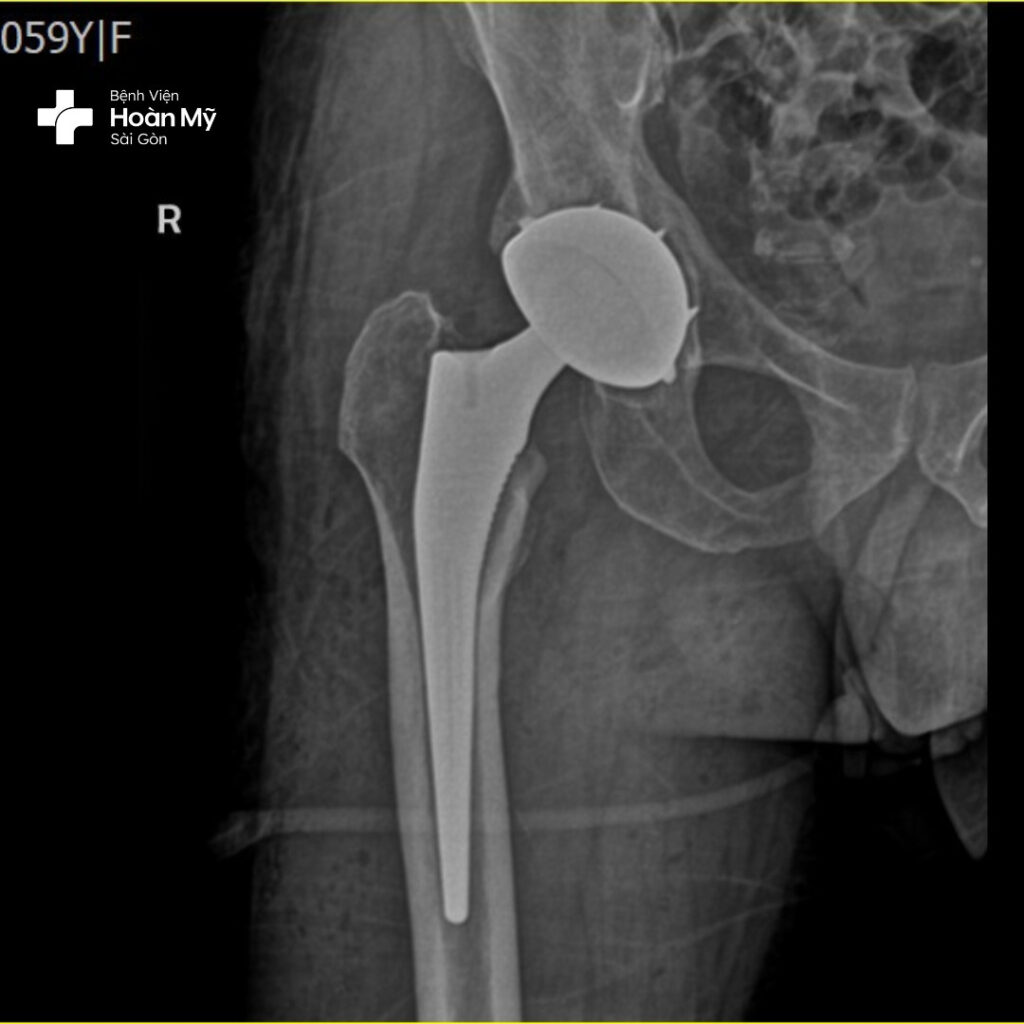

Hình ảnh X-quang sau phẫu thuật thay khớp háng của ông Đ.

Kỹ thuật thay khớp háng cùng lúc giúp ông Đ. giải quyết triệt để tình trạng hoại tử chỏm xương đùi với duy nhất một lần phẫu thuật. Điều này không những giúp tiết kiệm về mặt thời gian, khi người bệnh không phải đối mặt với hai lần phẫu thuật (thông thường lần phẫu thuật thứ hai phải cách lần phẫu thuật đầu tiên ít nhất 1-2 tháng), đồng thời tiết kiệm chi phí điều trị, giúp tâm lí người bệnh ổn định và lạc quan hơn.